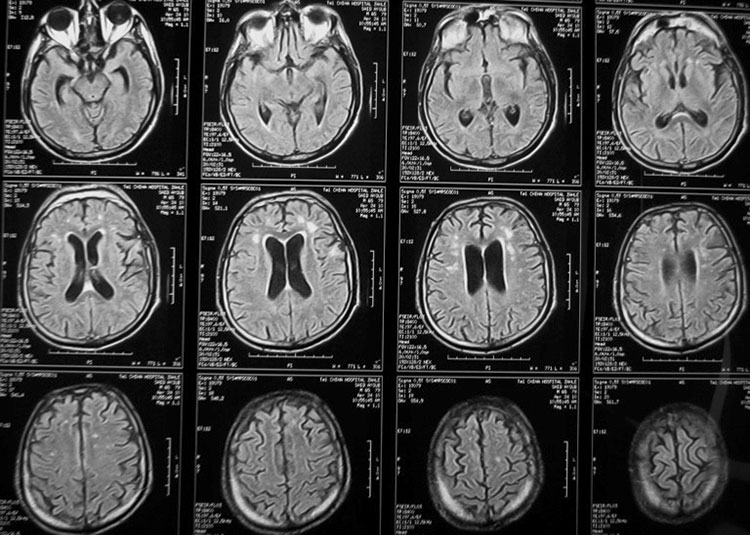

Подробное руководство по МРТ мозга спереди

В этом разделе вы найдете примеры снимков МРТ мозга в передней проекции, полезные советы для подготовки к обследованию, а также узнаете, что можно увидеть на таких изображениях.

МРТ головного мозга, что позволяет выявить?

Что показывает МРТ головного мозга

Что скрывает МРТ головного мозга